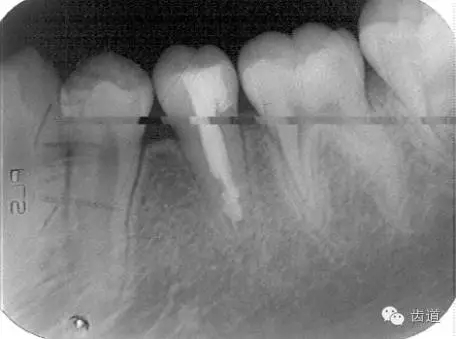

術(shù)后

術(shù)后199日

術(shù)后1084日